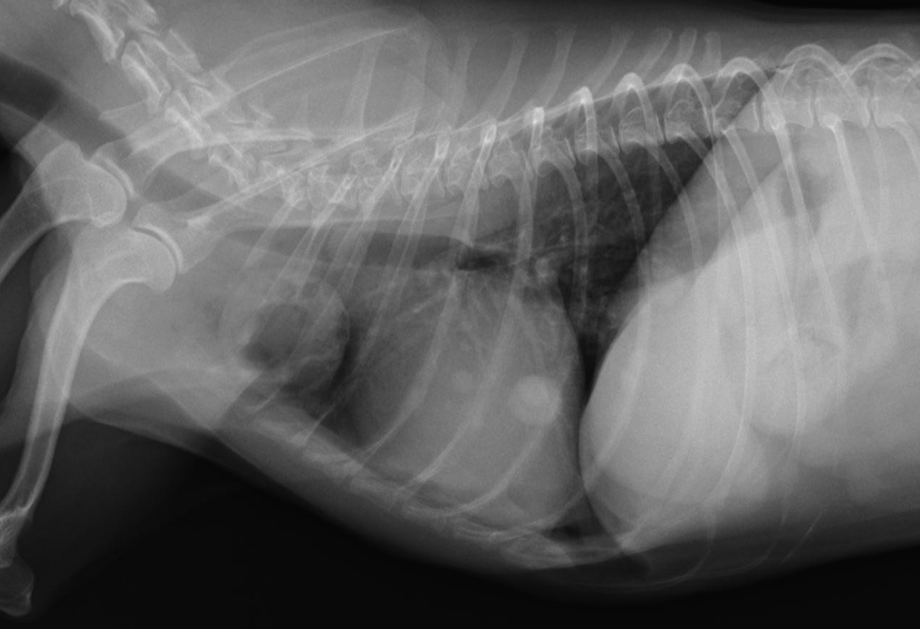

劇症膵炎による膵壊死、化膿性腹膜炎を呈した猫。

ねこちゃんの膵炎のなかでも急性に発病して重症化しやすい病気です。

case.1

雑種猫、6歳齢、去勢雄

predonisolone、ampicilline、enrofloxacin、nafamostat、maropitant、metoclopramide CRI、静脈輸液、経鼻チューブフィーディングにより急性期治療実施。